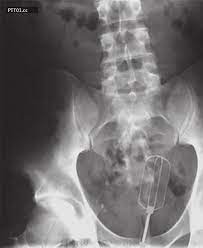

Kazayla Giren Nesneler

O Şişe Oraya Bakın Nasıl Girmiş…Röntgen filmlerinden çıkan akılalmaz şeyler Röntgen filmlerinden “akıl almaz şeyler Hastane koridorlarına düşenler bilir…